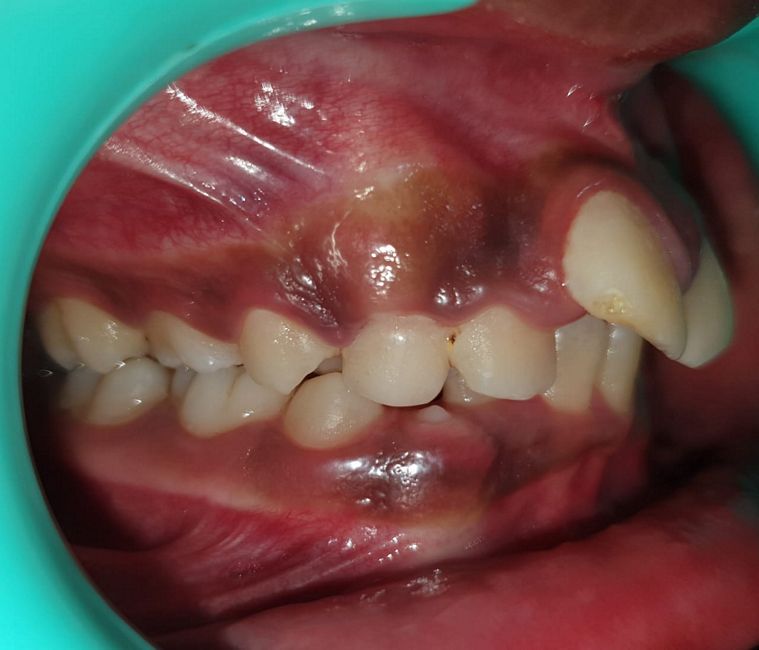

Malocclusion Type: Anterior Cross Bite

Mechanics: Self-Ligating Appliance (3M Smart Clip) Maxillary arch

MBT Mechanics (3M) Mandibular arch

Treatment: Dental Class I Malocclusion with anterior crossbite treated using Different Appliance in the upper and lower arches.